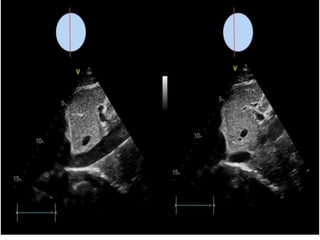

interperation

Can it replace CVP measurement?